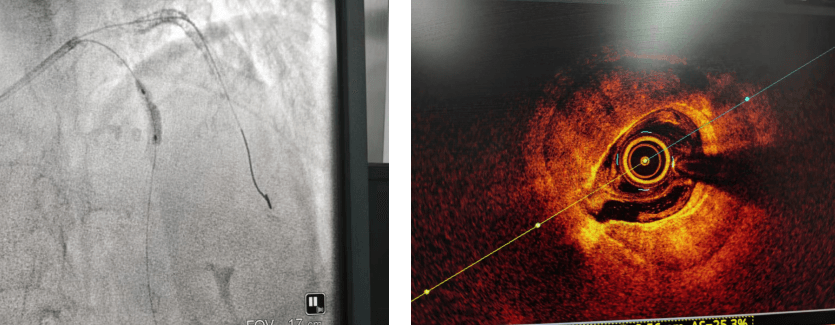

沖擊波球囊使用前球囊無法充分?jǐn)U張,OCT提示病變處環(huán)形鈣化

沖擊波球囊使用后復(fù)查OCT